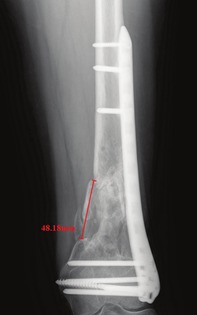

Results: According to the specified criteria, 55 distal femur fracture cases were ultimately included, with 38 cases in the LLP-only group and 17 cases in the DP fixation group. In terms of surgical and follow-up information, there were no statistical differences in healing status, but there were statistically significant differences in average blood loss (p = 0.013), metaphyseal bone defect size (p < 0.001), Lysholm score (p = 0.003), and EQ-5D score (p = 0.010). Notably, compared to other parameters, the size of the fracture defect exhibited the highest correlation (0.69) with healing outcomes. In logistic regression analysis, the defect size (OR 1.052, 95% CI 1.008-1.098, p = 0.021) was independently associated with the healing outcome. Upon further analysis, non-healing cases in the LLP-only group were predominantly associated with A3, C2, and C3 type fractures, with 83.3% of these patients presenting metaphyseal defects exceeding 15 mm.